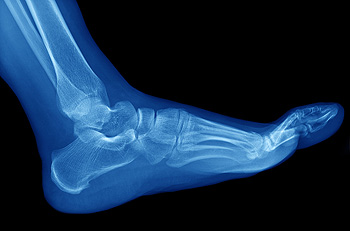

Running is a well-known sport that is loved by many people. However, without the proper knowledge of technique and equipment, many people can suffer running injuries. To avoid these types of injuries, it’s beneficial to gain knowledge on specific prevention tips you can practice while performing the sport. Strengthening your body is an important step in this process. Activation exercises can be useful to look into and perform before you go on a run, that way your body is prepared for physical activity. Increasing the intensity of your runs must be done gradually or your body will react negatively. Another factor in injury prevention is proper footwear. Your shoes should fit comfortably and also offer the necessary support features for the type of running you enjoy. For more information on how to prevent running injuries, please consult with a podiatrist for professional advice and care.

How to Prevent Running Injuries

Many common running injuries are caused by overuse and overtraining. When the back of the kneecap starts wearing out and starts causing pain in your knee, this is commonly referred to as runner’s knee. Runner’s knee is a decrease in strength in your quadriceps and can occur if you’re not wearing properly fitted or supporting shoes. To prevent runner’s knee, focusing on hip strengthening is a good idea, as well as strengthening your quads to keep the kneecaps aligned.

What Are Some Causes of Running Injuries?

- One cause of a common running injury is called iliotibial band syndrome.

- Plantar fasciitis is also another common injury.

- Stress fractures can occur from overtraining, lack of calcium, or even your running style.

Best Ways to Prevent Running Injuries

- Wear footwear that fits properly and suits your running needs.

- Running shoes are the only protective gear that runners have to safeguard them from injury.

- Make a training schedule. Adding strengthening exercises as well as regular stretching can help keep you strong and limber and can lessen the possibility of injuries.

- Stretching keeps muscles limber; this will help you gain better flexibility.

If you have any questions, please feel free to contact our office located in Richmond, VA . We offer the newest diagnostic and treatment technologies for all your foot care needs.